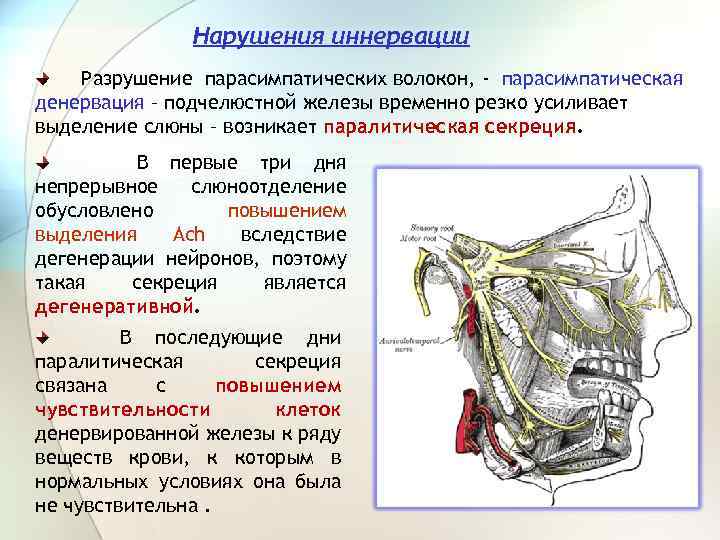

Нарушения иннервации Разрушение парасимпатических волокон, - парасимпатическая денервация – подчелюстной железы временно резко усиливает выделение слюны – возникает паралитическая секреция. В первые три дня непрерывное слюноотделение обусловлено повышением выделения Ach вследствие дегенерации нейронов, поэтому такая секреция является дегенеративной. В последующие дни паралитическая секреция связана с повышением чувствительности клеток денервированной железы к ряду веществ крови, к которым в нормальных условиях она была не чувствительна.